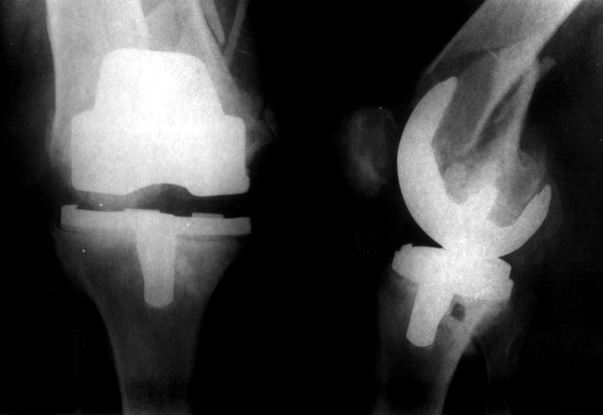

Добрый день! В нашу больничку поступил пациент после бытовой травмы - упал, подвернув ногу. На RG-граммах перелом дистального метаэпифиза бедренной кости. Пациент спутанно рассказывает, где и как он лечился раньше.10 лет назад - коррегирующая остеотомия по поводу деформирующего артроза коленного сустава, 3 года назад в 1 градской больнице г. Москвы выполнено эндопротезирование коленного сустава,площадка большеберцовой кости, со слов пациента, деформировалась около года назад (на фоне остеопороза). Сейчас получил травму в результате падения с высоты собственного роста.Что посоветуете?

на снимке признаки loosening и тибиального и феморального компонентов я думаю нужна ревизия если нет возможностей то артродез и конечно исключить инфекцию . успехов .

Учитывая высокую вероятность уже имеющейся нестабильности тибиального компонента и развившуюся при травме нестабильность бедренного, имеет смысл удаление обоих компонентов, реэндопротезирование конструкцией, имеющей возможность интрамедуллярного закрепления на длинном стержне (NexGen LCCK (Zimmer), AGC (Biomet), RT-Solution (Plus Endoprosthetik) и т.п.), параллельно выполнить остеосинтез винтами, серкляжами, пластиной - что окажется лучше, решить во время операции.

Мне представляется следующее: Если дистальный отдел бедра расколот и в сагиттальной и во фронтальной плоскостях, как видно на рентгенограммах, и при этом есть смещение отломков относительно друг друга и бедренного компонента эндоаротеза, разве от может оставаться стабильным? В случае отсутствия проблем с тибиальным компонентом, можно было бы надеяться только на остеосинтез и стабилизацию, но если предполагается ревизия в ближайшие месяцы/год, то не лучше ли за один раз решить несколько проблем?